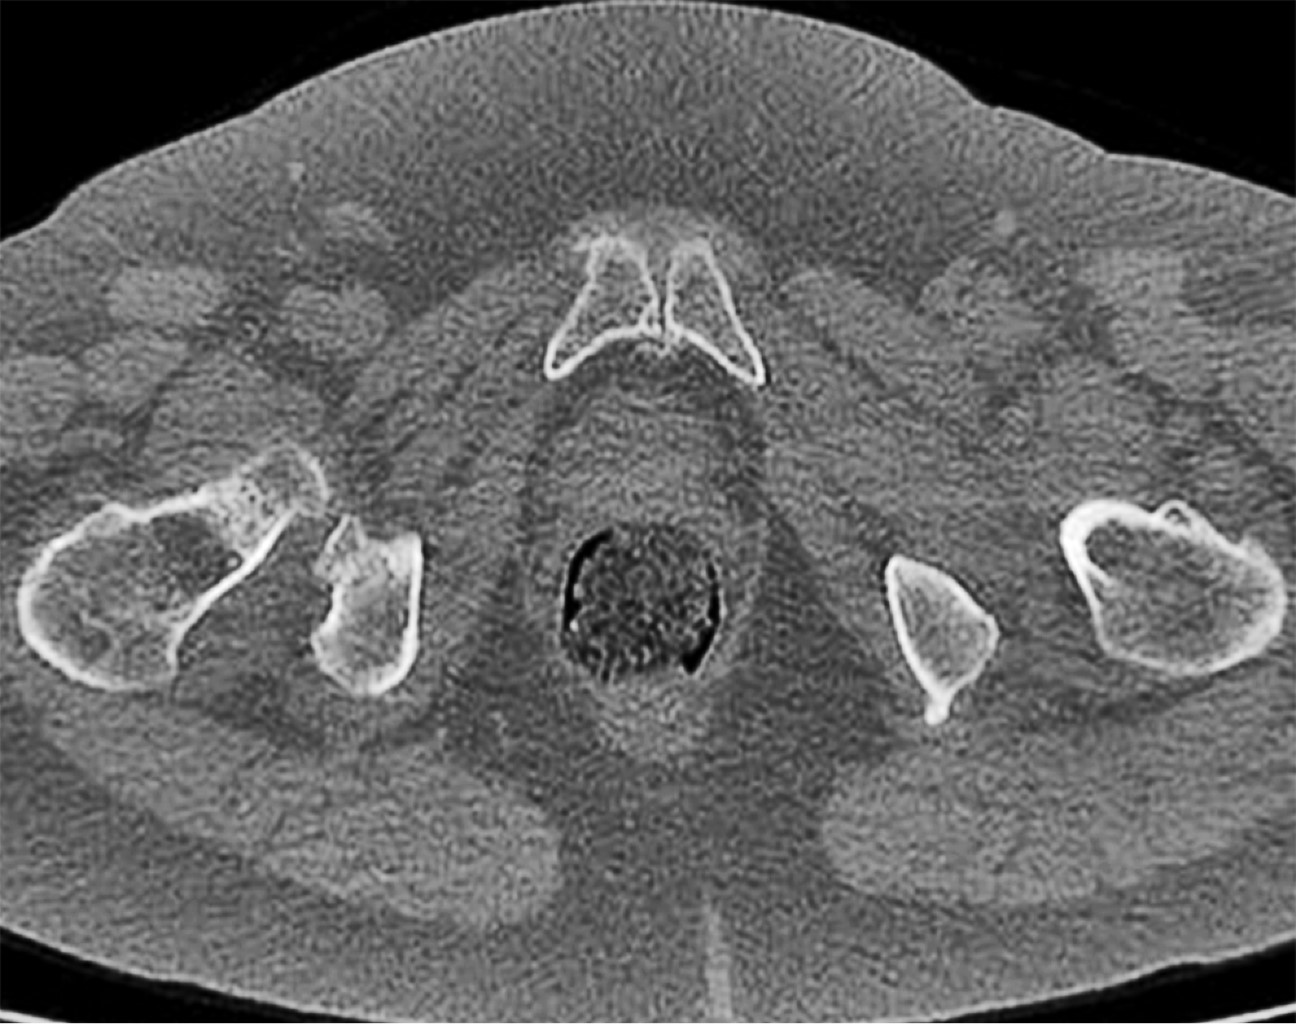

Figura 4

Se seleccionaron dos pacientes de 65 y 72 años. Ambas presentaron dolor en la sínfisis que les limitaba las actividades de la vida diaria. Una de ellas realizaba actividad física moderada que había tenido que cesar por completo debido a las molestias continuas. Se realizaron estudios de imagen que comenzaron con radiografías simples de pelvis (Figura 3).

Posteriormente se solicitó una tomografía computarizada (TC) de pelvis en el que se confirmaban los cambios degenerativos (Figuras 4 y 5) y una resonancia magnética que mostraba hallazgos de inflamación en las sínfisis compatibles con osteítis de pubis, asociados a edema de la musculatura adyacente. Ambas pacientes estuvieron realizando sesiones de fisioterapia y toma de antiinflamatorios no esteroideos (AINE) y corticoides con escasa mejoría. La infiltración de bupivacaina junto con corticoide fue el tratamiento más efectivo, pero pasados los dos meses la clínica, se reprodujo y se planteó en ese momento la opción quirúrgica. Las puntuaciones en la escala visual analógica (EVA) previamente a la cirugía fueron de 8 y 9, respectivamente.